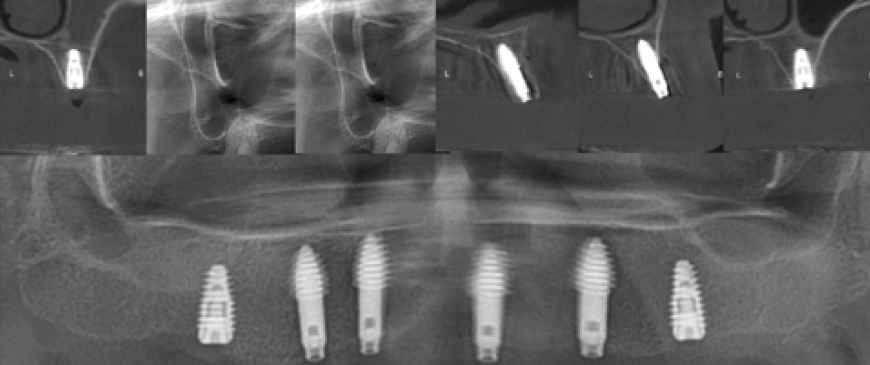

Fig 7

Post-surgery panoramic and CBCT radiographs show that all implants in the posterior and anterior regions were placed in stable positions. Since the fixture threads of all implants were securely integrated into the bone, a secondary surgery was scheduled approximately 10 weeks later.

Post-surgery panoramic radiograph. Immediately after the surgery, impressions were taken to prepare provisional prostheses.

Fig 9

Post-surgery CBCT radiograph. All ARi implant threaded parts were properly positioned within the alveolar bone

Fig 10